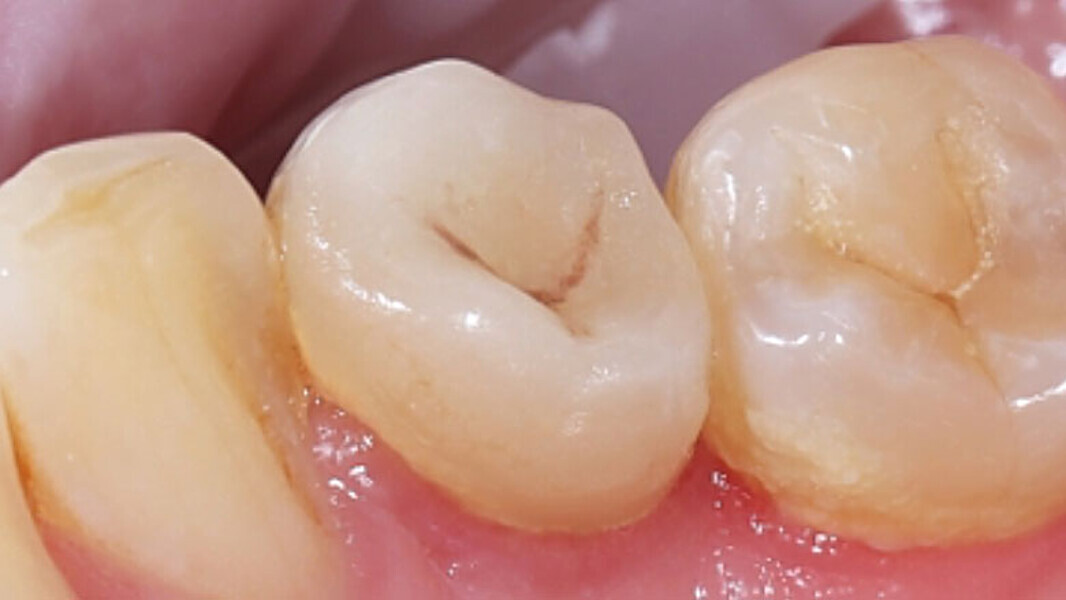

Fig. 13. Vista oclusal de la endocorona colocada de forma totalmente adhesiva.

Fig. 14. Resultado: integración altamente estética de la restauración durante la revisión al cabo de seis meses.